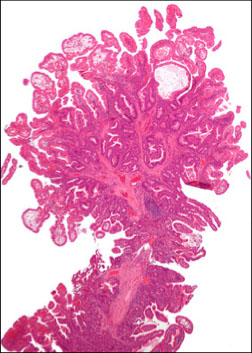

Micro: Lined by mucinous mucosa with arborizing thin complexly branching muscle bundles

Hamartomatous polyp c sm muscle